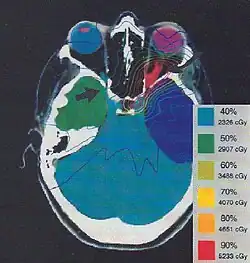

Celem leczenia jest zachowanie lub poprawienie wzroku. Nierzadko nie wdraża się leczenia poprzestając na obserwacji; wieloletni przebieg choroby bez pogorszenia widzenia nie jest rzadki. Standardowe leczenie polega na radioterapii i (lub) resekcji guza.